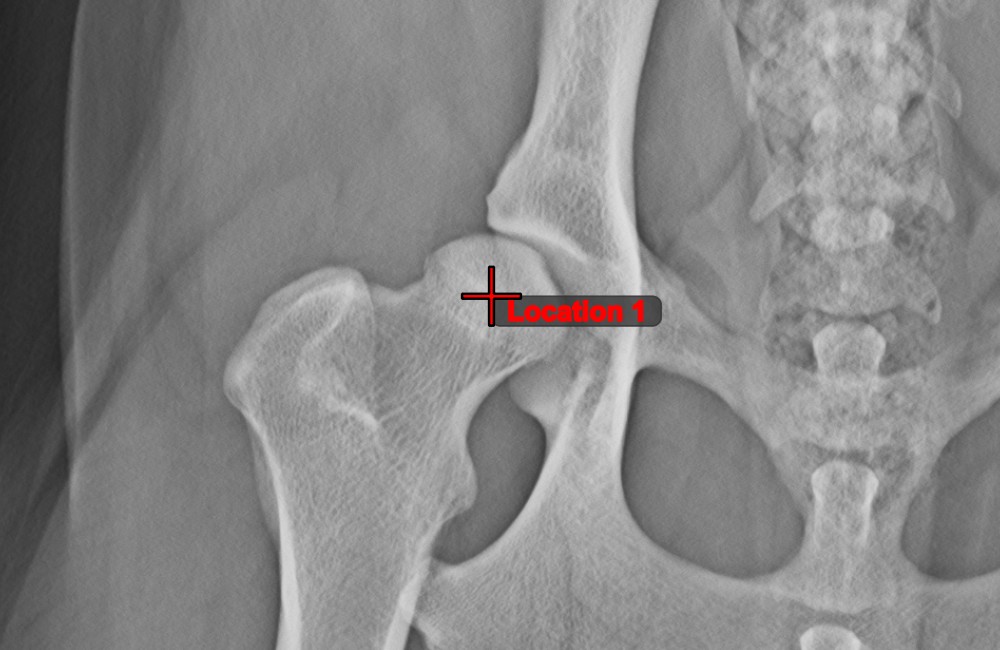

Measurement Point¶

Measurement Point tool. Each point is assigned with a letter for better identification.Select/Move Item tool. Select the point by using the assigned mouse button of the tool, and then move it freely anywhere on the image.